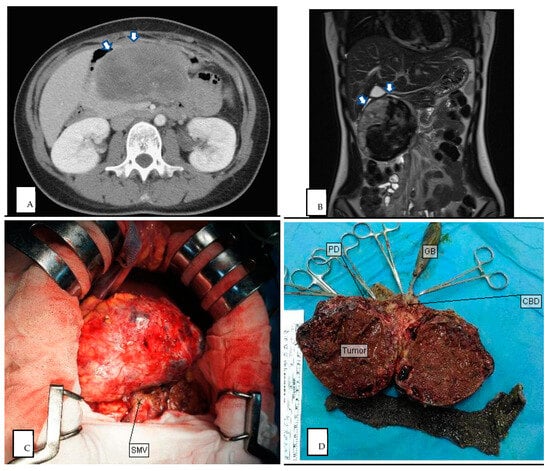

Figure 2.

(A) Preoperative CT image of SPN in pancreatic head (axial plane, venous phase). (B) Preoperative MRI image of SPN in pancreatic tail (coronal plane, T2 weighted). (C) Intraoperative photography of SPN in pancreatic head. (D) Cross section of intraoperative specimen in pancreatic head, showing a tumor composed of mixed cystic and solid components with hemorrhagic areas. White arrow demarcates region of pancreatic tail mass. PD pancreaticoduodenectomy, GB gallbladder, CBD common bile duct.

All of our patients had preoperative radiologic findings in either US, CT, or MRI. Most showed typical features of SPN (Figure 2 and Figure 3), such as oval, exophytic, and regular capsulated lesions with a mixed cystic and solid component but were almost entirely solid or cystic with thick walls [7]. Preoperative imaging studies included US (10/24 cases), CT (23/24 cases), and MRI (14/24 cases). In total, nine cases were diagnosed as SPNs based on preoperative imaging, four cases based on CT (17%), and five cases based on MRI (36%) (Table 1). The CT modalities are shown in Table 2; all tumor margins were clear in preoperative images. No hemorrhage, parenchyma atrophy, or invasion of adjacent vessels and abdominal organs was seen. More irregular shaping was seen in SPNs of the pancreatic head (p = 0.037). The cystic component was significantly more prominent in the SPN of the pancreatic tail (p = 0.035). Pancreas or bile duct dilation was mostly seen in the pancreatic head in our patient (p < 0.001).